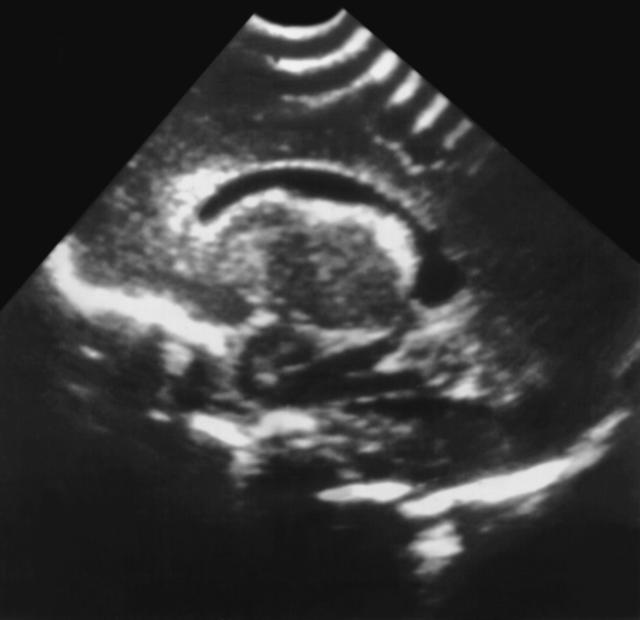

Рис. 1. Ультразвуковая картина головного мозга новорожденного с интравентрикулярным кровоизлиянием: умеренная вентрикуломегалия, неровность контуров сосудистого сплетения, тромб в затылочном роге бокового желудочка.